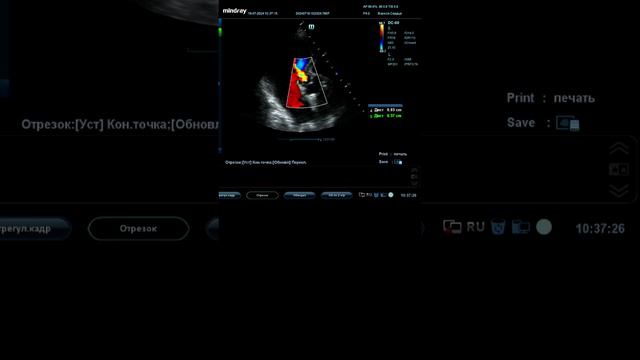

Видео: УЗИ щитовидной железы. Порядок выполнения

В этом видео рассказывается порядок выполнения ультразвукового исследования щитовидной железы. #узищитовидки #щитовиднаяжелеза #узищитовиднойжелезы #узи,